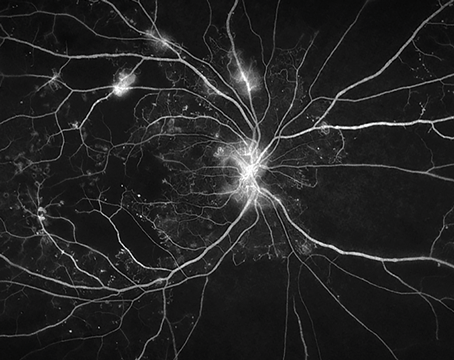

Optimizing oral fluorescein in angiography